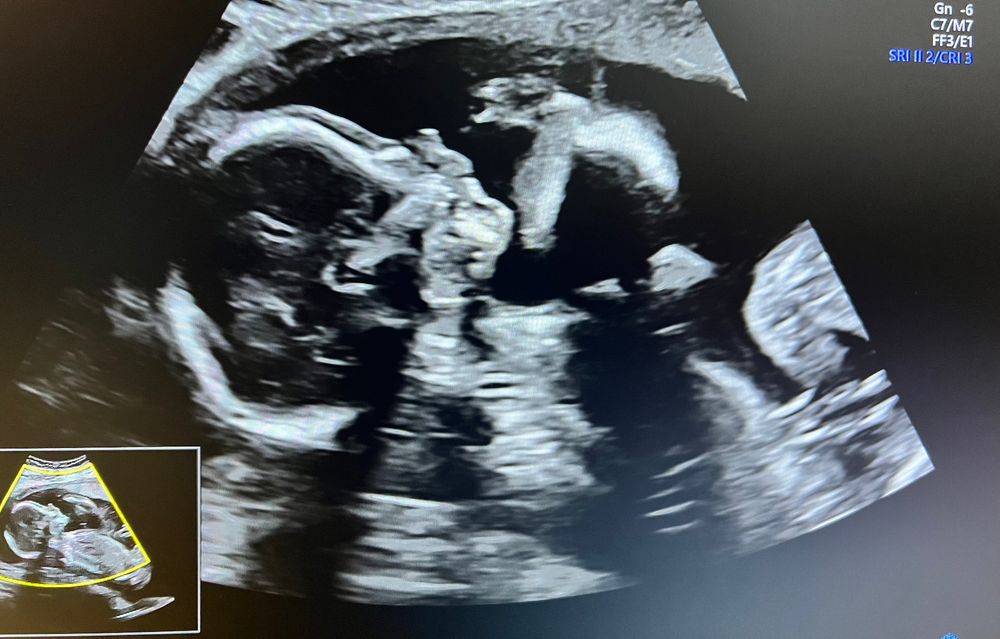

Второй скрининг 🙈

Мои пирожочки сегодня ездили на второй скрининг, врач Узи назвала их синхронистами - лежат прям как батона , головами вниз и синхронно ) намерили все как положено . Я, конечно ж , опять пустила скупую женскую слезу когда включили сердцебиения . Дама отворачивалась и меня отправили погулять , что б глянуть лицо и там все. После половины стаканчика кока-колы стала очень сговорчивой и устроила просто дикие танцы , все удалось померить и разглядеть .

мальчуган 295 г, девочка 275 г.

А на втором снимке они не головенками друг к другу?) а то у меня один товарищ уверенно так другого по черепушке ногами дубасил)